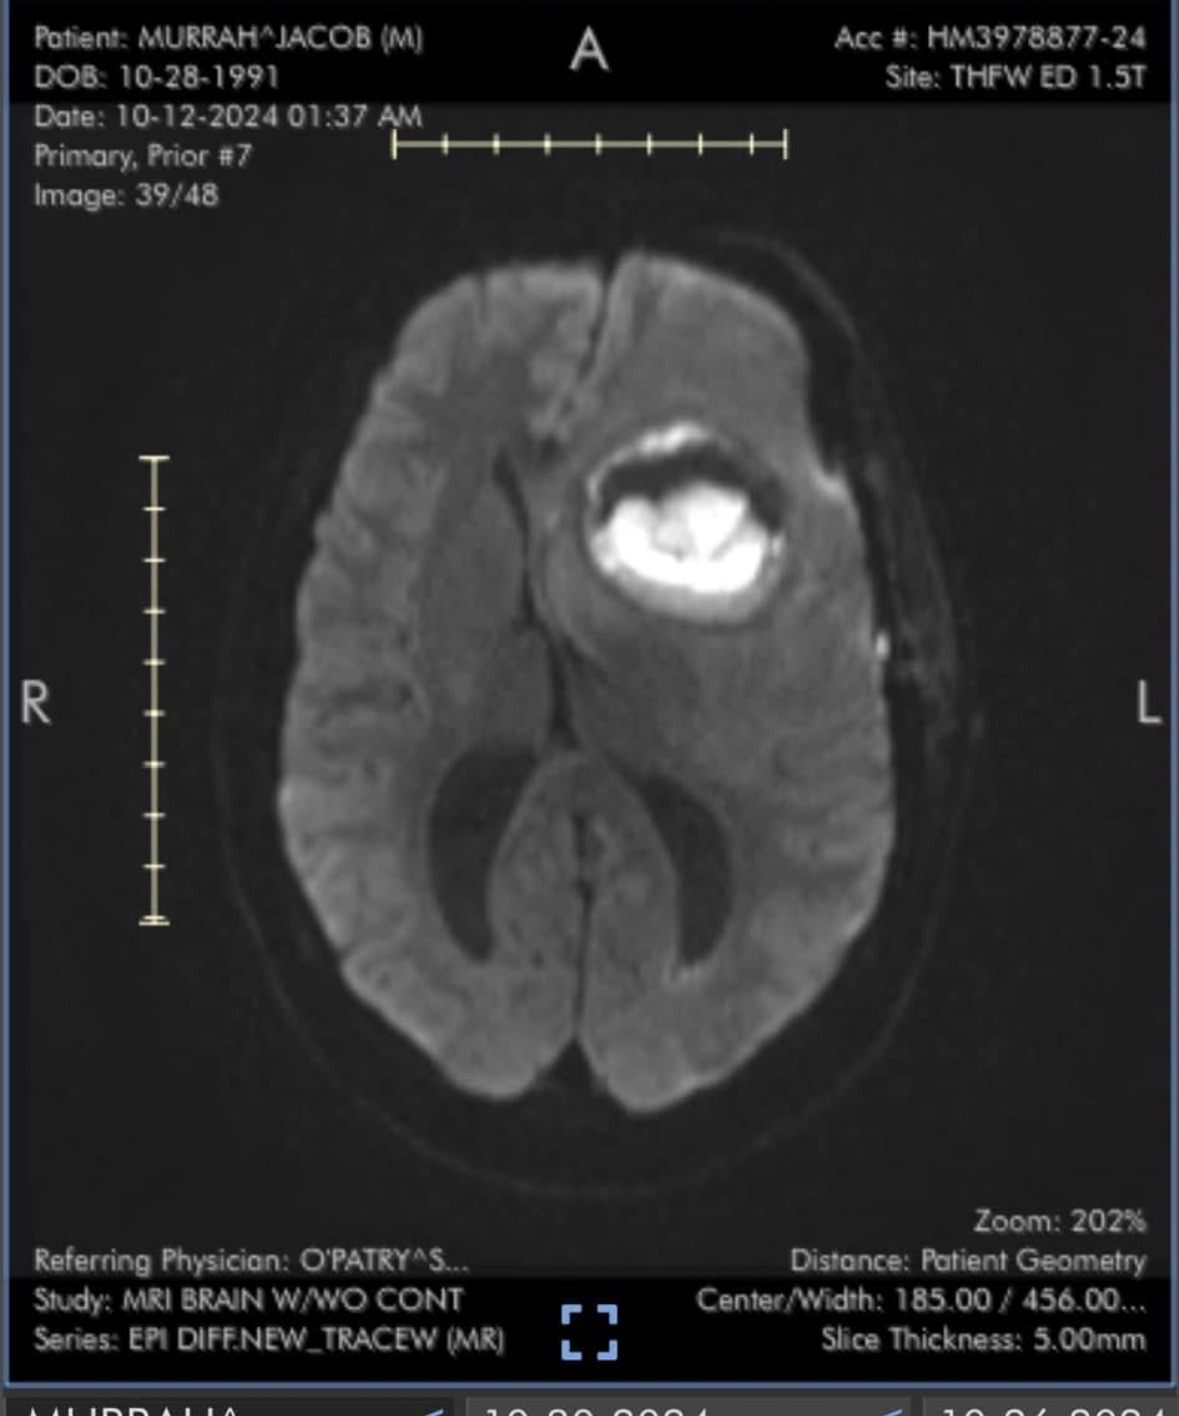

This is Jacob Murrah , On September 30th I was told I had a brain abscess and was septic and they were not sure I would make it . I had brain surgery on October 1st 2024. They were only able to remove about 25% at that time without causing severe damage to the brain. I have been on the strongest antibiotic they make through a picc line since early October 2024. It will not be removed until the abscess is completely gone .The good news is it is shrinking but it will still take time to be completely gone . I am on a long term work leave now . I am not receiving my full paycheck right now since I went from short term to long term work disability. I could really use some help until I am able to return back to work. Thank you all for helping when I was in the hospital you have no idea how much all your kindness has meant to me ! Anything would be so helpful and appreciated. I also have Zelle that is connected to my cell phone number. Private message me or my mom if you prefer Zelle and do not have my number. Thank you so very much for all the thoughts and prayers.